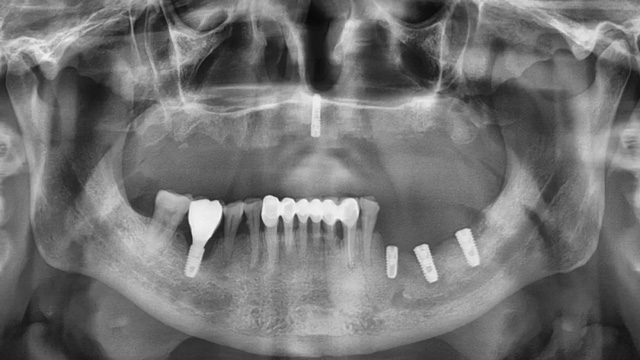

经CBCT检查所见,沈老师的口腔情况比较复杂:下面原有的四颗种植牙只有一颗有牙冠,其余三颗种植体情况尚可,可以安装牙冠,上半口牙列缺失,牙槽骨里还埋着一个种植体。“这颗植体的位置没有骨板,不能受力,没有安装牙冠的条件。好在它位置在正中,不影响种植手术和牙冠修复。”

幸运的是,这颗遗留种植体的周围组织没有炎症,无用也无害,为了减少创伤,易华波医生没有拔除它。

治疗前口腔全景片